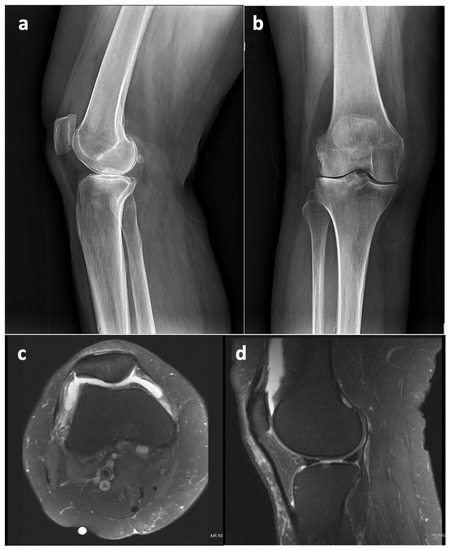

There were no systemic symptoms indicative of infection such as a history of fever or chills. An examination revealed an antalgic gait, diffuse moderate knee swelling with associated warmth, a range of motion of 0 to 100° flexion without an extension lag, no ligamentous instability, and a neutral limb alignment. Her laboratory values were as follows: erythrocyte sedimentation rate (ESR) 124 mm/h (reference range 0–20 mm/h), C-reactive protein (CRP) 17.7 mg/dL (reference range: 0.0–1.0 mg/dL). A knee aspiration was performed, which demonstrated 25 mL of straw-colored native fluid, 77% neutrophils, and negative cultures after 14 days. NexGen sequencing (MicroGenDx, Orange Country, FL, USA) was also performed on a second aspiration, and the aspiration was also negative for bacterial DNA fragments. The radiographs were normal and showed no evidence of implant loosening (Figure 2). Several aspirations were performed previously that showed no evidence or signs of PJI.

Figure 2. X-rays from 9 September 2022 ((a)—lateral view, (b)—anterior–posterior view, (c)—Merchant view). Right total knee arthroplasty (TKA) was reidentified with components in anatomic alignment without fracture.